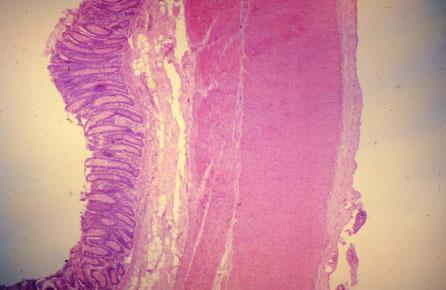

VIII-2 (4) Slide 61, Colon (H&E). (L-R) Epithelium with crypts of Lieberkühn, muscularis mucosa, submucosa, muscularis externa, serosa and mesothelium. Note there is no villus.